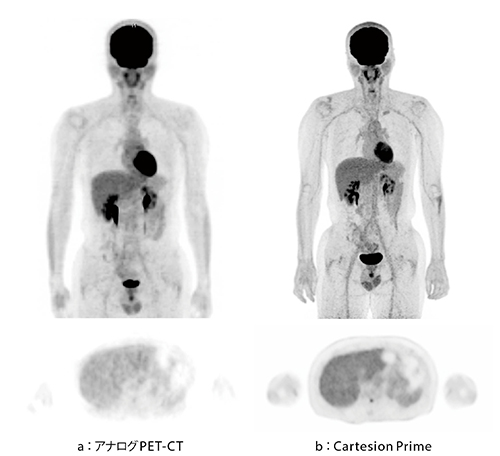

図1 全身PET-CT画像(健常ボランティア)

半導体検出器を搭載したCartesion Prime(b)はTOF時間分解能が高く、見た目の分解と感度が向上し、アナログPET-CT(a)に比べて精細かつ均一性の高い画像が得られている。